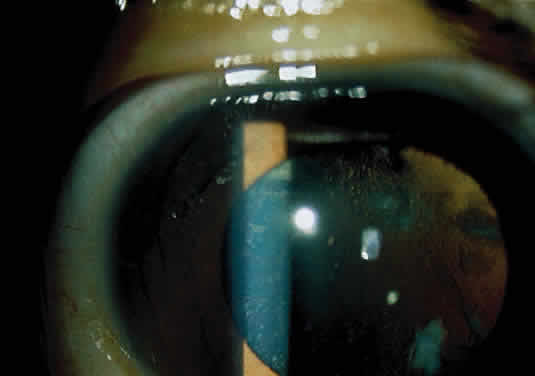

Corneal clouding, the most common ocular feature, generally is not present before 10 years of age45 (Fig. 7), but one of us (EIT) has observed it in three Lebanese siblings younger than 10 years of age. The corneal epithelium and Bowman's layer appear normal under the slit lamp, and there is a homogeneous clouding of the corneal stroma. There is no retinal dystrophy.46

Fig. 7. Corneal opacification in a child with Morquio syndrome (MPS IV).